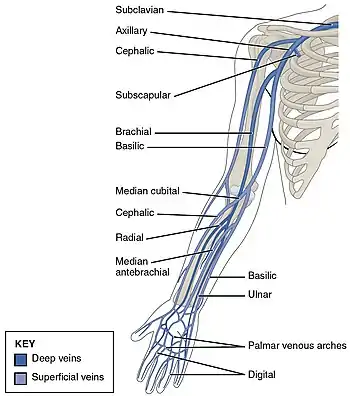

DVT often develops in the calf veins and "grows" in the direction of venous flow, towards the heart.[42][103] DVT most frequently affects veins in the leg or pelvis[9] including the popliteal vein (behind the knee), femoral vein (of the thigh), and iliac veins of the pelvis. Extensive lower-extremity DVT can even reach into the inferior vena cava (in the abdomen).[104] Upper extremity DVT most commonly affects the subclavian, axillary, and jugular veins.[11]

In DVT in the arm, the first (topmost) rib can be surgically removed as part of the typical treatment when the DVT is due to thoracic outlet syndrome or Paget–Schroetter syndrome. This treatment involves initial anticoagulation followed by thrombolysis of the subclavian vein and staged first rib resection to relieve the thoracic outlet compression and prevent recurrent DVT.[146]

DVT occurs in the upper extremities in about 4–10% of cases,[11] with an incidence of 0.4–1.0 people out of 10,000 a year.[5] A minority of upper extremity DVTs are due to Paget–Schroetter syndrome, also called effort thrombosis, which occurs in 1–2 people out of 100,000 a year, usually in athletic males around 30 years of age or in those who do significant amounts of overhead manual labor.[69][147]